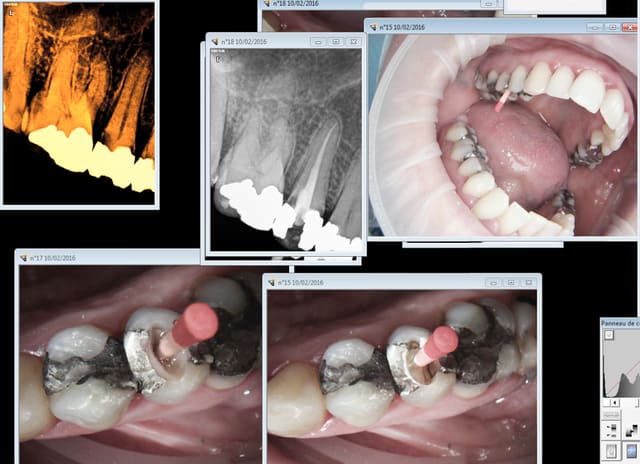

il y a une évolution/révolution pour notre cabinet c'est

de posséder un CBCT ;on voit des images peu visibles sur

une radio rétro ou une panoramique 2d

vraiment une révolution puisque on peut visualiser le

fameux MV2 des molaires sup. (il est là ou pas!!!)

ce rendre compte des courbures ;on a la longueur LT

de manière précise sur le logiciel qui peut confirmer le localisateur d'apex

Voici un exemple de couplage microscope opératoire/cbct

RTE 36 en octobre2012 ;3 heures de RTE pour recherche de canaux sous micro inserts ultrasons/il y avait une LIPOE

digue+hypo+système R-endo microméga instruments à mains

vérification au CBCT en 2016

disparition des LIPOE

ici on obtient une guérison apicale